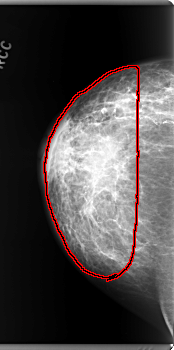

C_0159_1.RIGHT_MLO

RIGHT_MLO LINES 5944 PIXELS_PER_LINE 2952 BITS_PER_PIXEL 12 RESOLUTION 50 OVERLAY

FILE: C_0159_1.RIGHT_MLO.OVERLAY

TOTAL_ABNORMALITIES 1

ABNORMALITY 1

LESION_TYPE MASS SHAPE IRREGULAR MARGINS ILL_DEFINED

ASSESSMENT 5

SUBTLETY 5

PATHOLOGY MALIGNANT

TOTAL_OUTLINES 1

BOUNDARY